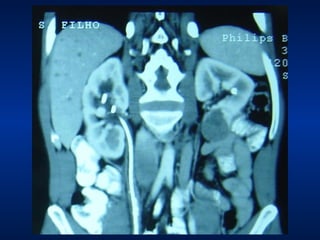

Nefrectomia radical laparoscópica Indicações: Tumores: T1-T3aN0M0 Ideal: até 10cm de tamanho Contra-indicações: Extensão tumoral extra-renal Invasão de VR e/ou VCI

Nefrectomia radical laparoscópicaIndicações: Tumores: T1-T3aN0M0 Ideal: até 10cm de tamanho Contra-indicações: Extensão tumoral extra-renal Invasão de VR e/ou VCI